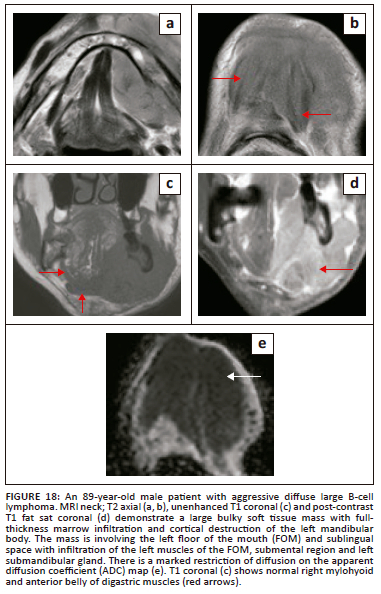

Lymphomas contribute 14% of head and neck malignancies and the vast majority are non-Hodgkin lymphomas (96%). Lymphoma of the oral cavity is generally uncommon and constitutes only 5% of oral malignancies. Primary non-Hodgkin lymphoma of the mandible is extremely rare, accounting for only 0.6% of extranodal lymphomas and 8% of mandibular malignancies.27,28

At imaging, these rare FOM lymphomas present as characteristically bulky, homogeneous soft tissue masses with a varying degree of significant contrast enhancement and pronounced restriction of diffusion. The osseous abnormalities can appear as ill-defined lytic destruction or an infiltrative pattern with invasion and widening of the inferior alveolar nerve canal. Typical radiological findings are presented in Figure 18.